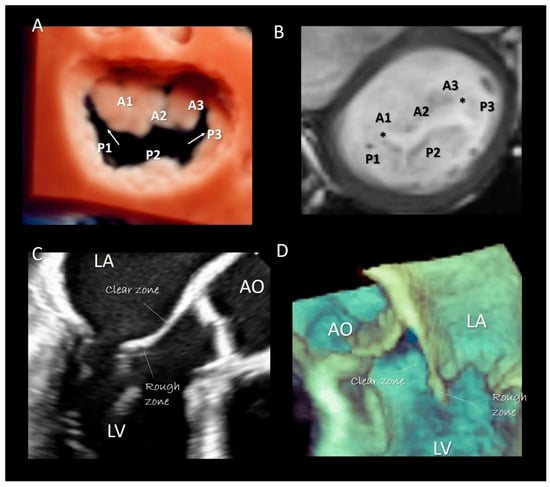

Two deep commissures separate the mitral veil in two halves. The anterior (or aortic) mitral leaflet (AML) and the posterior (or mural) mitral leaflet (PML). At both ends of the zones of apposition between the aortic and mural leaflets can often be found commissural leaflets, which occasionally can be extensive. The AML has an almost triangular-shaped surface and its hinge line covers approximately 1/3 of the annular circumference. The posterior leaflet has a more rectangular-shaped surface and its hinge line covers the remaining 2/3. As the AML is longer than the PML, the area of the two surfaces is equal. In the majority of normal MV, the PML is divided by two incisures into three parts, called scallops: P1 (lateral), P2 (central), P3 (medial). Conversely, the anterior leaflet has no identifiable incisures. However, surgeons call the areas of the AML opposing the corresponding scallops of the posterior leaflet A1, A2, and A3, (Figure 5A,B). Inspection of the ventricular surface of both leaflets reveals two distinct areas: the rough and clear zones. The rough zone receives the insertion of chordae tendineae and presents a “corrugate” and thicker aspect, while the clear zone, lacking chordal insertion, has a smoother, thinner and sometimes translucent appearance (Figure 5C,D). Interestingly the rough zones correspond on their atrial aspect to the area where leaflets juxtapose each other during the systole. The vast majority of chordal attachment is therefore within the coaptation area sharing the mechanical stress with the leaflets. Lack of coaptation between leaflets causes not only a mitral regurgitation but also an abnormal traction on chordae tendineae with an increasing risk of chordal rupture.

Figure 5.

(A) 3D TEE with a new volume rendering algorithm from an overhead view, showing the two commissure (arrows) and the P1, P2, P3 scallops of the posterior leaflet. A1, A2, A3 are the corresponding segments of anterior leaflet. (B) CMR cross-section short-axis at the level of mitral leaflets showing the commissures (asterisks) and the scallops. (C) 2D TEE and (D) 3D TEE cross-section long-axis views showing the rough and clear zones.